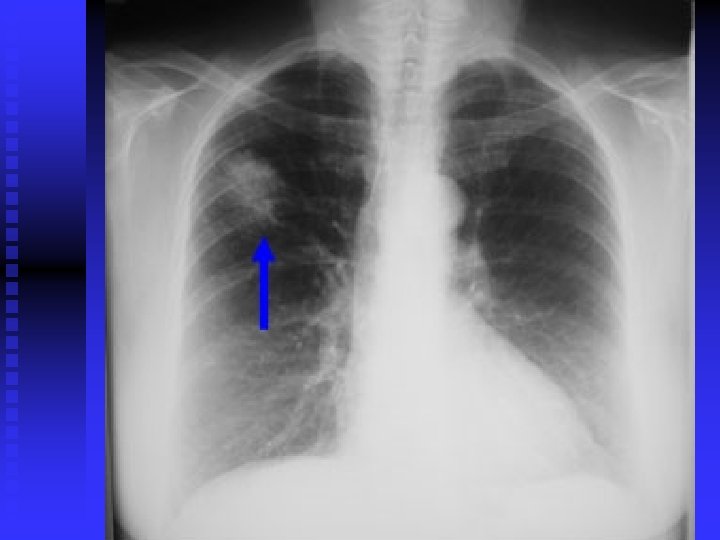

Case 1 50 year old Asian man n 30 pack year history of smoking n Strong family history of malignancy n Persistent cough for > 6 months n Frequent visits to GP: several course of antibiotics n Admitted to St. Helier Hospital with haemoptysis and weight loss n Cervical lymphadenopathy, clubbed n

Case 1 Tumour seen right upper lobe and right intermediate bronchus as Bronchoscopy n Poorly differentiated adenocarcinoma n Referred to RMH: Stage 4 disease, so palliative chemotherapy only n n Early chest X-ray and referral after onset of symptoms may have made a difference !